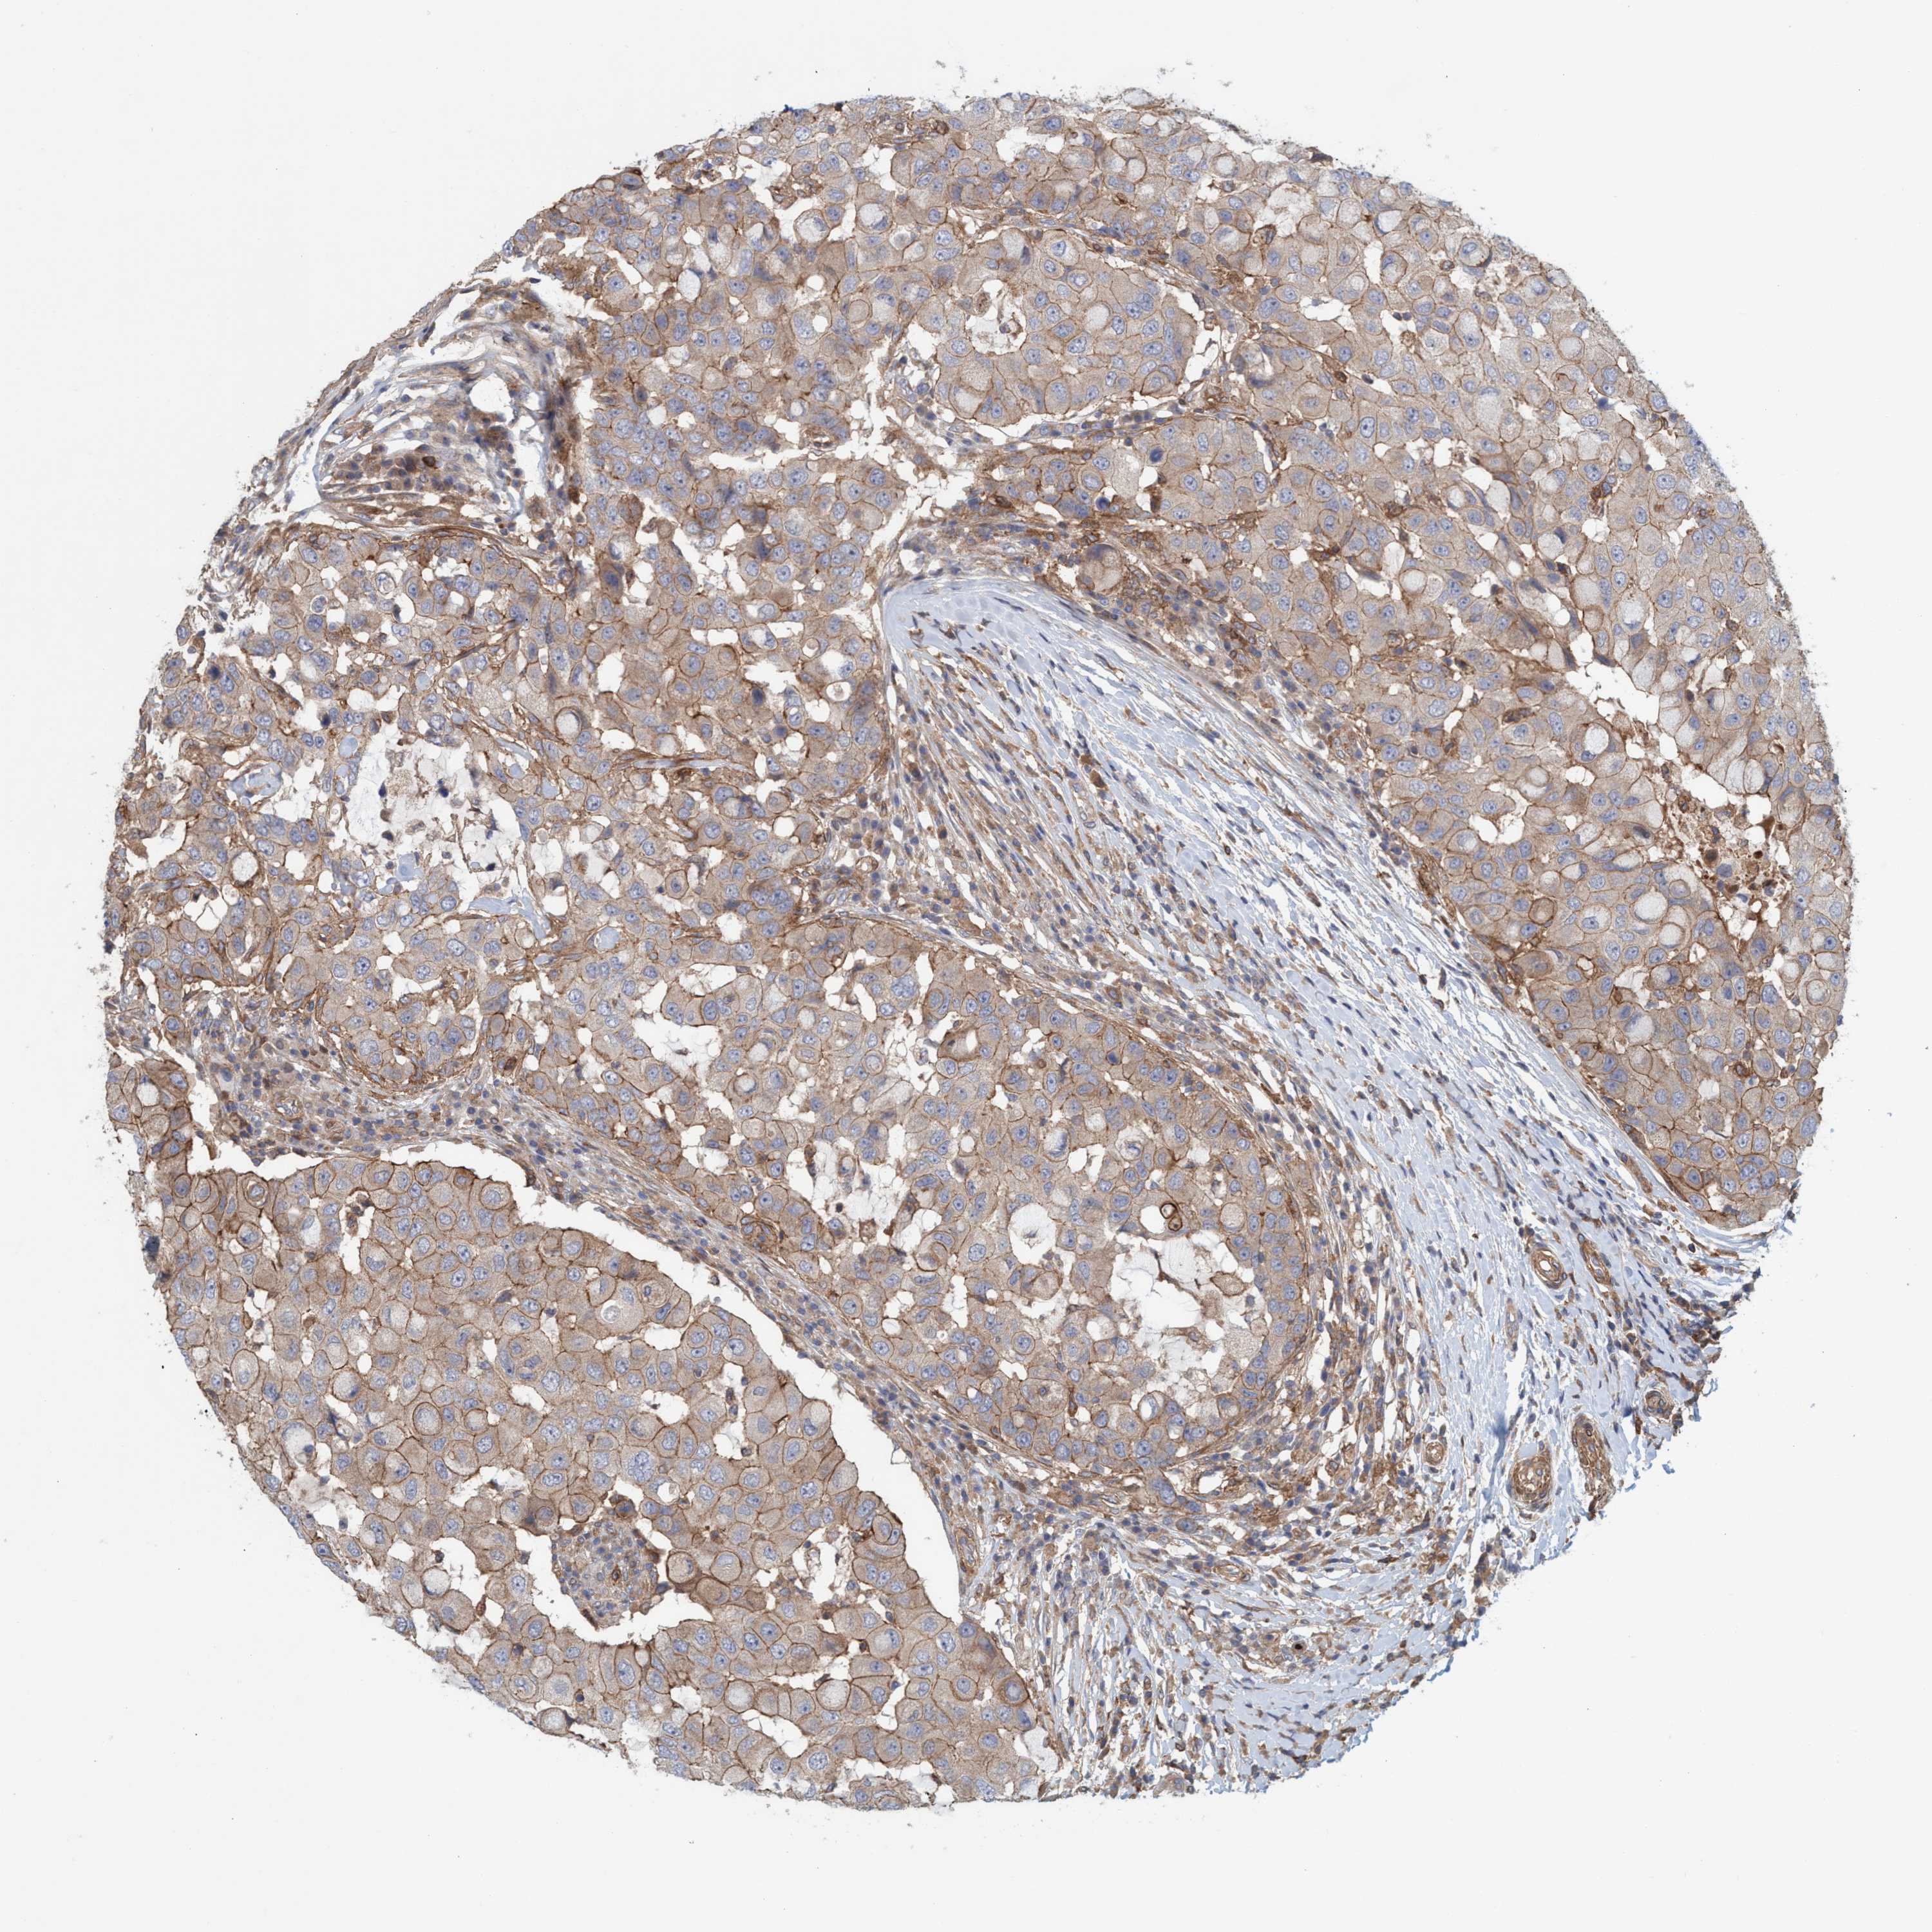

CANCER BREAST CANCER Show tissue menu

BRCA TCGA BRCA VALIDATION PROTEIN EXPRESSION